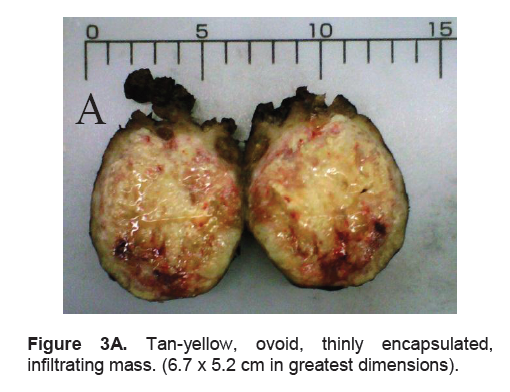

The right lobe measured 8.3 x 6.0 x 4.3 cm, and weighed 119.5 grams with a tan brown surface covered with fibrous tags (Figure 3A). Cut sections showed an ovoid mass, 6.7 x 5.2 cm in greatest dimensions, with a thin capsule and yellow-tan, gritty to mucoid cut surface with areas of hemorrhage and necrosis. The tumor infiltrated and replaced normal thyroid parenchyma and was surrounded by a thin capsular rim. Tissue sections of the right lobe revealed an infiltrative tumor composed of an admixture of pleomorphic cells, spindle cells and occasional tumor giant cells (Figure 3B). There were small areas showing reminiscent papillary or microfollicle pattern, while some areas showed large epithelioid or multinucleated tumor cells with bizarre nuclei (Figure 3C). Capsular (Figure 3D) and vascular (Figure 3F) invasion were present with extensive tumor necrosis. The uninvolved right and left lobes showed multinodular colloid goiter with lymphocytic thyroiditis. It was signed out as an Anaplastic (undifferentiated) thyroid carcinoma of the right lobe.

Figure 3A. Tan-yellow, ovoid, thinly encapsulated, infiltrating mass. (6.7 x 5.2 cm in greatest dimensions).